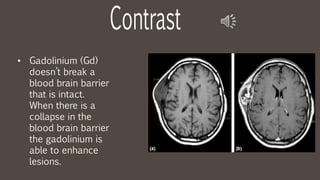

• Gadolinium (Gd)

doesn’t break a

blood brain barrier

that is intact.

When there is a

collapse in the

the gadolinium is

able to enhance

lesions.